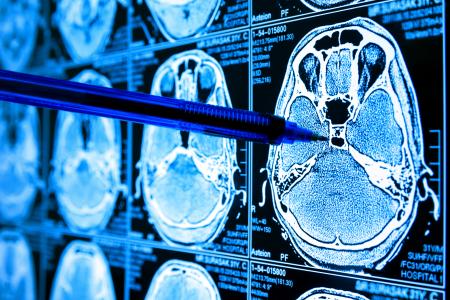

GLIOBLASTOME : Ettouffer les cellules tumorales

Laissant de côté la stratégie la plus immédiate, qui consiste à cibler la glycolyse dans les tumeurs malignes, cette équipe de la Columbia University, de la City University of New York et de l’Ulm University s’attaque au métabolisme mitochondrial qui permet la respiration des cellules tumorales. En ciblant précisément des enzymes pertinentes pour la respiration cellulaire, une voie critique pour la production d'énergie cellulaire, sous forme d'adénosine triphosphate (ATP). L’équipe démontre ainsi dans la revue Oncotarget l’efficacité des inhibiteurs de la respiration mitochondriale à étouffer les glioblastomes.

Des travaux importants, alors qu’il existe déjà des inhibiteurs de l'histone désacétylase (HDAC) approuvés par l’Agence américaine FDA qui peuvent exercer cet effet profond sur le métabolisme énergétique des cellules tumorales, y compris dans le glioblastome. Les chercheurs précisent qu’en raison de l'impact de ces inhibiteurs sur le métabolisme, ils ont fait l’hypothèse que les dérivés d’imipridone, qui suppriment la respiration cellulaire, pourraient agir en synergie avec ces composés pour améliorer de manière significative la destruction des cellules de glioblastome.

L’étude confirme que le ciblage du métabolisme énergétique mitochondrial semble réalisable grâce à plusieurs composés médicamenteux. Ces composés démontrent des effets anticancéreux in vivo et, des recherches récentes ont déjà suggéré quels sont les patients les plus susceptibles de bénéficier de ces traitements.